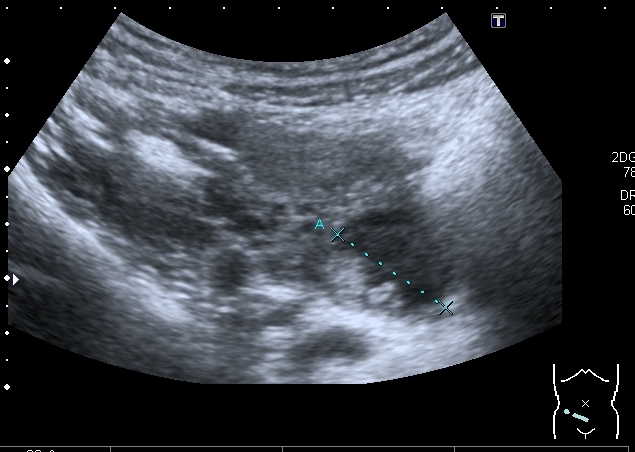

Правый яичник увеличен, с солидно - кистозными образованиями

Высказал предположение о множественных папиларных цистаденомах яичников. Хотелось бы узнать, насколько я прав.

Думаю, что на папиллярную цистаденому это похоже.

Никогда не встречал мультилокулярное и билатеральное поражение , но покопавшись в книгах, вычитал, что двухстороннее поражение составляет от 6 до 32% случаев. Очень подходит клиника - боли в животе, увеличение живота, дизурия. Дальнейший прогноз - 50% малигнизация.